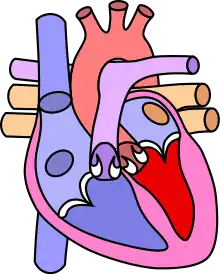

![]() | |

| Diagram of a healthy heart and one with tetralogy of Fallot | |

The cause is typically not known.[5] Risk factors include a mother who uses alcohol, has diabetes, is over the age of 40, or gets rubella during pregnancy.[5] It may also be associated with Down syndrome.[10] Classically there are four defects:[4]

- pulmonary stenosis, narrowing of the exit from the right ventricle

- a ventricular septal defect, a hole between the two ventricles

- right ventricular hypertrophy, thickening of the right ventricular muscle

- an overriding aorta, which allows blood from both ventricles to enter the aorta

Four malformations

"Tetralogy" denotes four parts, here implying the syndrome's four anatomic defects.[2] This is not to be confused with the similarly named teratology, a field of medicine concerned with abnormal development and congenital malformations (including tetralogy of Fallot). Below are the four heart malformations that present together in tetralogy of Fallot:

| Pulmonary Infundibular Stenosis | A narrowing of the right ventricular outflow tract. It can occur at the pulmonary valve (valvular stenosis) or just below the pulmonary valve (infundibular stenosis). Infundibular pulmonic stenosis is mostly caused by the overgrowth of the heart muscle wall (hypertrophy of the septoparietal trabeculae),[29] however, the events leading to the formation of the overriding aorta are also believed to be a cause. The pulmonic stenosis is the major cause of the malformations, with the other associated malformations acting as compensatory mechanisms to the pulmonic stenosis.[30] The degree of stenosis varies between individuals with TOF and is the primary determinant of symptoms and severity. This malformation is infrequently described as sub-pulmonary stenosis or subpulmonary obstruction.[31] |

| Overriding aorta | An aortic valve with biventricular connection, that is, it is situated above the ventricular septal defect and connected to both the right and the left ventricle. The degree to which the aorta is attached to the right ventricle is referred to as its degree of "override." The aortic root can be displaced toward the front (anteriorly) or directly above the septal defect, but it is always abnormally located to the right of the root of the pulmonary artery. The degree of override is extremely variable, with 5-95% of the valve being connected to the right ventricle.[29] |

| Ventricular septal defect (VSD) | A hole between the two bottom chambers (ventricles) of the heart. The defect is centered around the most superior aspect of the ventricular septum (the outlet septum), and in the majority of cases is single and large. In some cases, thickening of the septum (septal hypertrophy) can narrow the margins of the defect.[29] |

| Right ventricular hypertrophy | The right ventricle is more muscular than normal, causing a characteristic boot-shaped (coeur-en-sabot) appearance as seen by chest X-ray. Due to the misarrangement of the external ventricular septum, the right ventricular wall increases in size to deal with the increased obstruction to the right outflow tract. This feature is now generally agreed to be a secondary anomaly, as the level of hypertrophy tends to increase with age.[32] |